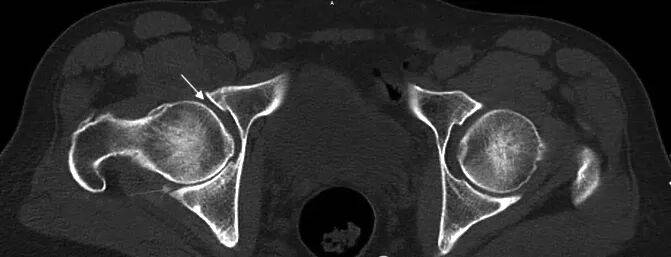

仔细看MRI片(图1),可见左侧股骨头(L)很圆,右侧股骨头不仅不圆且髋臼有内陷。将MRI片与CT片(图2)结合起来,可以明确诊断。CT片可见关节面下囊性变,关节间隙不等宽,周围还有骨质增生。